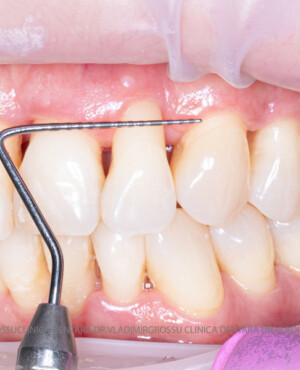

Aditia gingivală este o procedură chirurgicală ce corectează diverse probleme estetice și funcționale, cum ar fi recesiunea gingivală. În implantologia modernă, aditia de țesut moale este utilizată aproape în fiecare intervenție de inserție a implantului dentar pentru a asigura un aspect estetic natural și o bună integrare a implantului în cavitatea bucală.

Adiția osoasă are un rol crucial pentru poziționarea corectă și stabilă a implanturilor dentare. Clinica stomatologică Dr. Grossu din Chișinău promovează o abordare chirurgicală estetică și predictibilă, adaptată fiecărui caz în parte.

Medicii noștri au o vastă experiență atât în chirurgia estetică, cât și în protezarea cu un grad înalt de naturalitate, ceea ce ne permite să gestionăm cu succes și cele mai complexe cazuri.